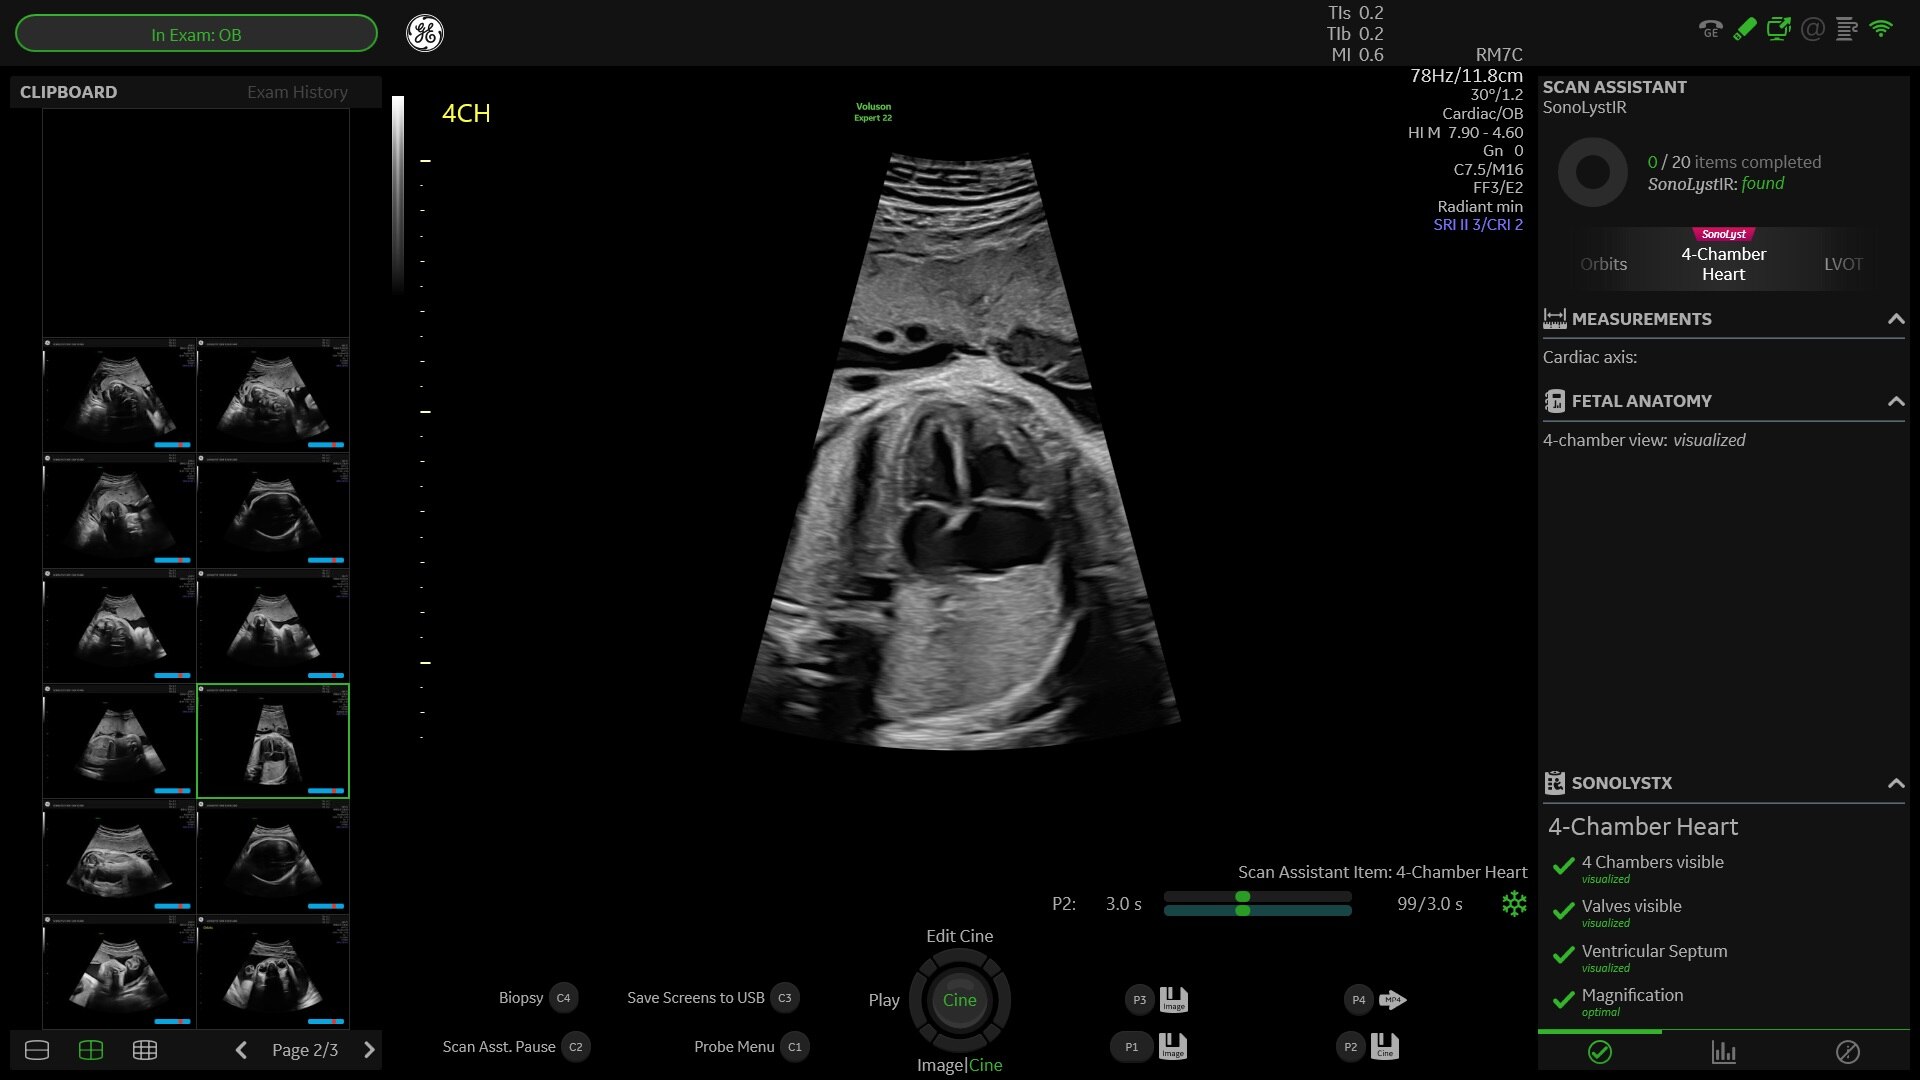

Sharp images, instant clarity

Discover extraordinary image clarity and precision